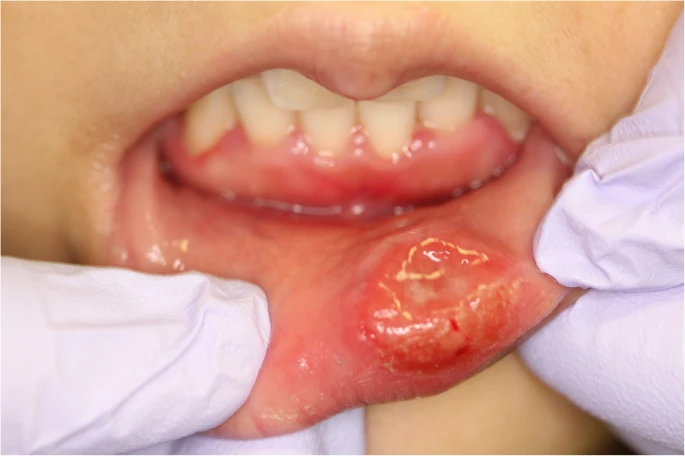

女性の梅毒症状写真・画像

第一期(初期症状)

初期硬結・硬性下疳

女性陰部

肛門

Genital ulcers caused by sexually transmitted agents

感染後約1ヶ月ほどで感染した部位かにしこり・潰瘍が出来ます。

また、鼠蹊部や頸部のリンパ節が痛みを伴わずに硬く腫れることもあります。

多くの場合は治療しなくても自然に症状が一旦消失しますが、梅毒への感染がなくなったわけではありません。

見た目よりも痛みが少ないことも特徴で、痛みが少なく、自然に症状が消失してしまうため医療機関を受診されずに放置されてしまうケースが多くあります。